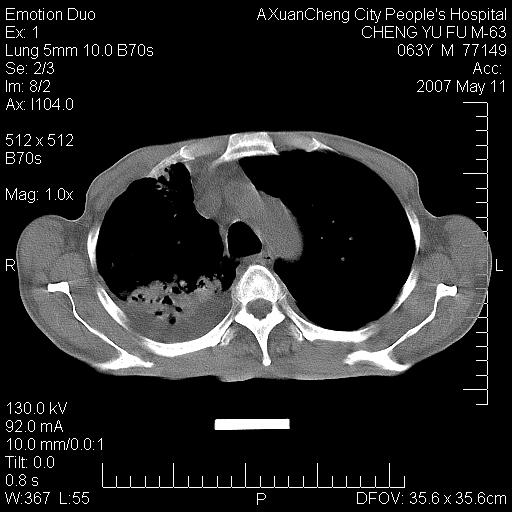

以下是引用小初学者在2007-5-11 19:32:00的发言:[br]1、首先考虑干酪性肺炎支气管播散[br]2、支气管肺泡癌待排

以下是引用zhangzhongshou在2007-5-11 19:30:00的发言:[br]细支气管肺泡癌可能性大。